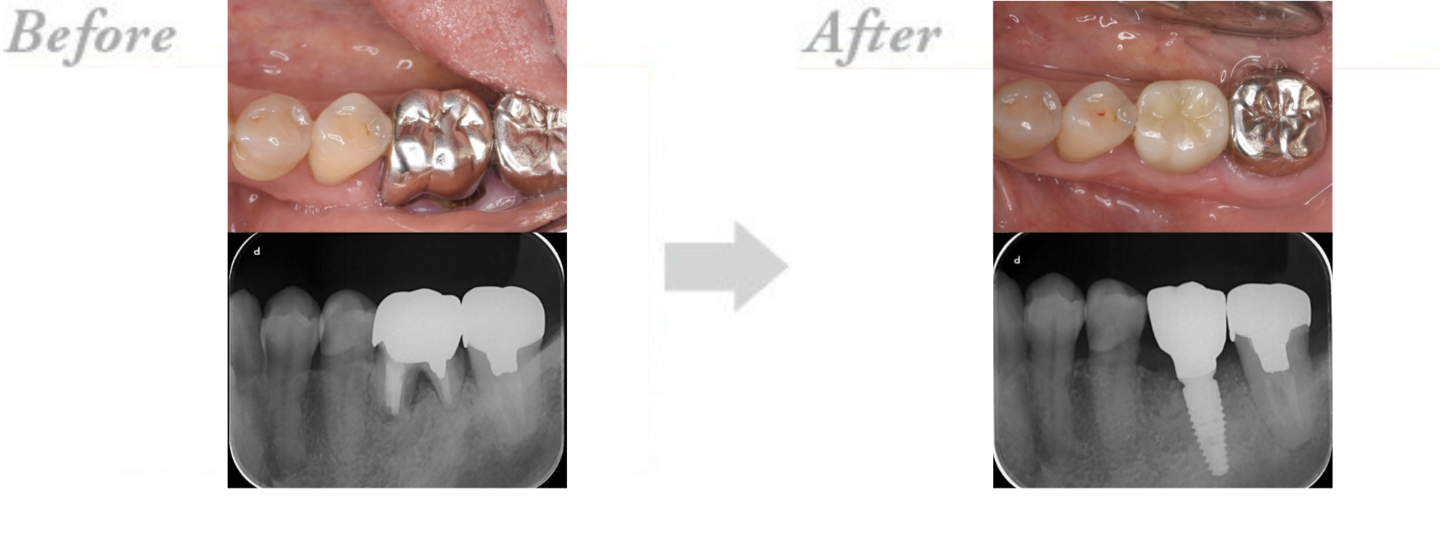

◆インプラント治療の実例 CASE4